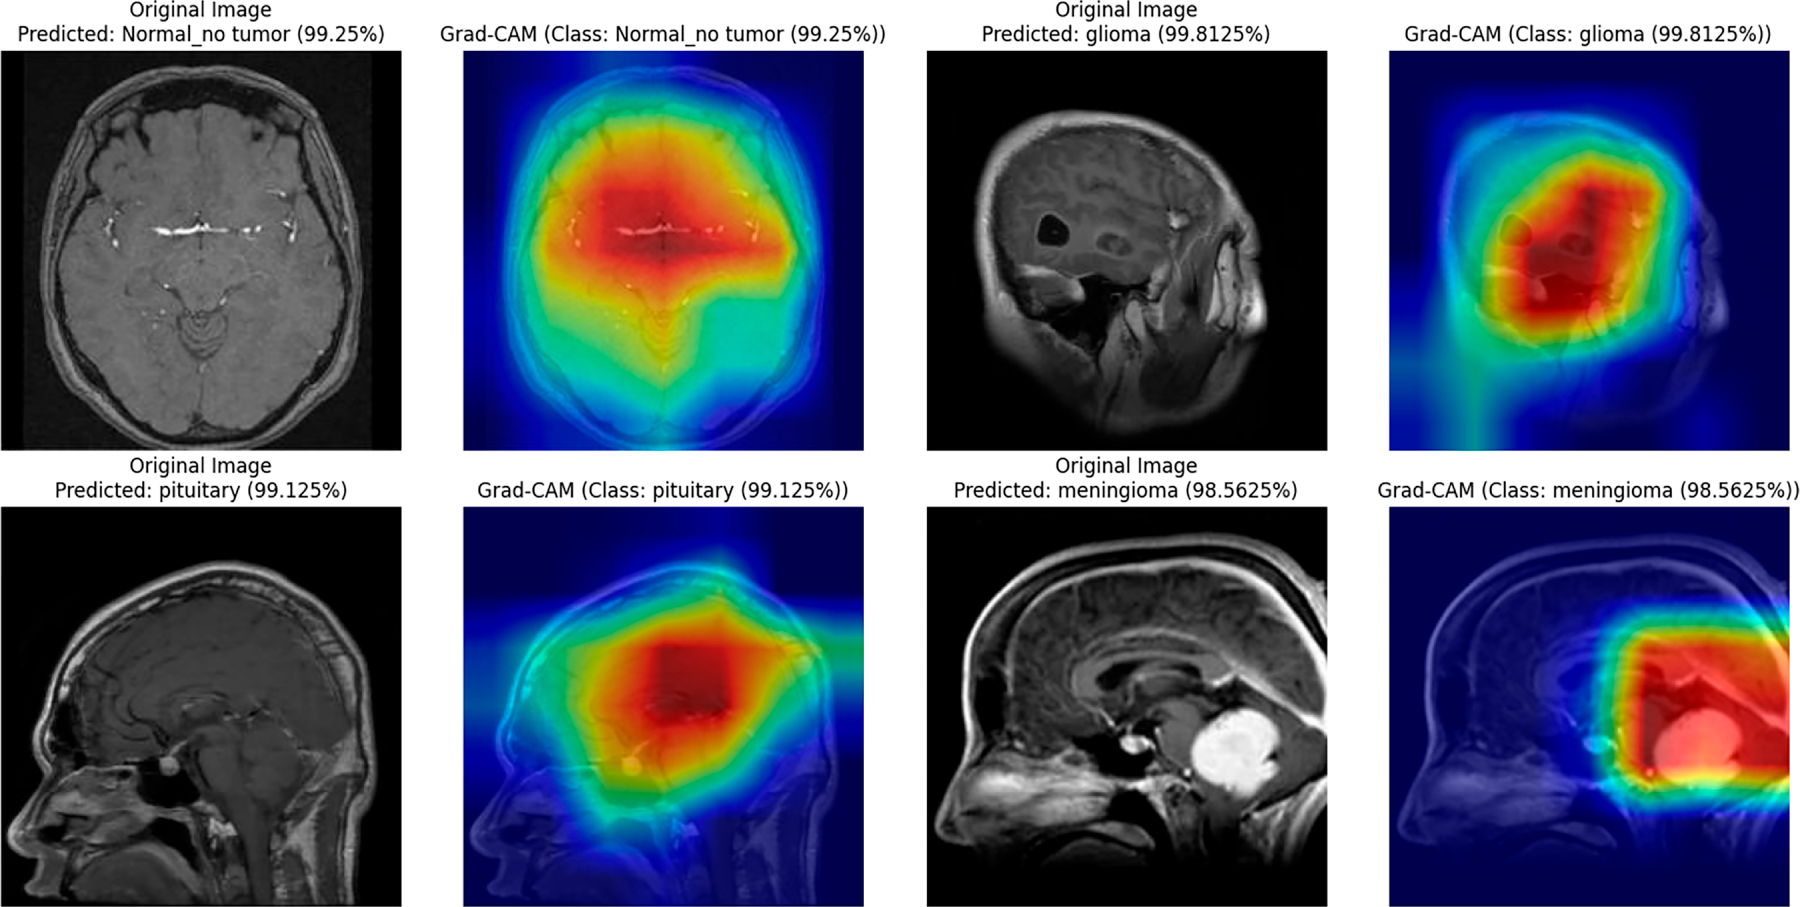

The interpretability of the student model was analyzed using Grad-CAM and LIME visualizations, complemented by faithfulness scores (Insertion and Deletion metrics) computed over 10 representative images per class. These analyses were conducted after achieving state-of-the-art accuracy, thereby confirming that high predictive performance aligns with stable interpretability. The confidence scores of the sampled images remained consistently high (average 0.99), indicating strong predictive certainty of the model. Grad-CAM visualizations (Fig. 9) clearly highlight the spatial regions with the greatest impact on predictions across all four classes, including normal, glioma, pituitary, and meningioma, accurately localizing tumor regions and supporting the model’s structural focus. LIME results (Fig. 10b) further delineate superpixels contributing to model decisions, while class-specific masks (Fig. 10a) were generated solely for visualization in the faithfulness evaluation, not for training purposes.

Figure 9: Grad-CAM visualizations for the student model across different brain tumor classes (glioma, pituitary, meningioma) and normal brain images.

Table 7 presents the Insertion and Deletion scores for both Grad-CAM and LIME. Notably, the normal class shows a low deletion score of 0.09 for Grad-CAM because removing non-informative regions in a normal brain has minimal effect on prediction, reflecting the absence of critical features to disrupt the model’s confident classification. Across all classes, the average insertion and deletion scores confirm that the highlighted regions consistently correspond to the model’s confident predictions (Insertion: 0.69 Grad-CAM, 0.73 LIME; Deletion: 0.45 Grad-CAM, 0.59 LIME).

In summary, combining Grad-CAM, LIME, and mask-based faithfulness metrics provides a comprehensive interpretability framework, ensuring transparency, high diagnostic accuracy, and confidence in both teacher and student models for neurodiagnostic applications.